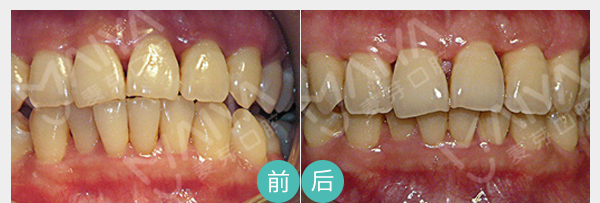

• 麦芽龈下刮治

麦芽龈下刮治术是用比较精细的龈下刮治器刮除位于牙周袋内根面上的牙石和菌斑,舒适无痛微创愈合快、深度去除牙龈层牙垢

适应症:牙龈萎缩、牙周炎症 导致的牙体敏感